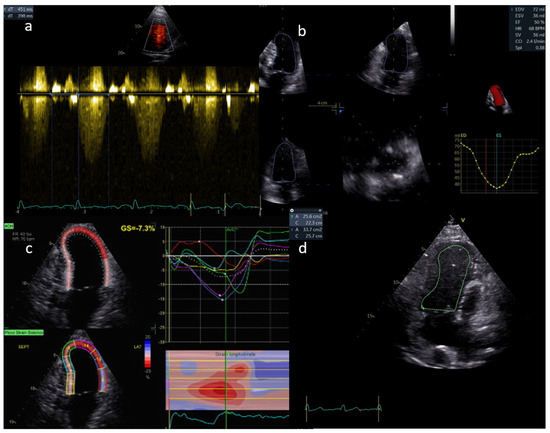

The lack of a subpulmonary ventricular pump results in non-pulsatile flow in the pulmonary vascular bed and Fontan pathway. As a result, the fluid dynamics of the stenoses will be more like a venous obstruction, and the Doppler flow gradient is frequently low. Therefore, the size of the Fontan connection and of the pulmonary arteries should be carefully examined. Any reduction and enlargement downstream should be taken into consideration and studied by both a continuous and a pulsed wave Doppler (Figure 2). A reduction in the variability of flow and a mean gradient as low as 3 mmHg can reflect a significant obstruction.

Figure 2. (a,b) Normal flow in the Fontan pathway; (c,d) mild flow acceleration through a stented extracardiac conduit.